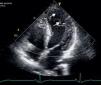

Mulher de 34 anos, com antecedentes de tabagismo, foi observada por palpitações rápidas com 12 anos de evolução. As queixas eram diárias, de curta duração e não se associavam a tonturas, síncope ou dor torácica. Não tinha antecedentes familiares de morte súbita, mas foi diagnosticado ao pai uma miocardiopatia dilatada idiopática. Como parte da avaliação realizou eletrocardiograma que revelou bradicardia sinusal, 36 b.p.m., critérios de hipertrofia ventricular esquerda, progressão anormal da onda R nas precordiais, ondas q não patológicas e alterações inespecíficas da repolarização ventricular em DII, DIII, aVF, V3-V6 e QTc longo. O ecocardiograma mostrou cavidades cardíacas não dilatadas, com boa função sistólica biventricular. O ventrículo esquerdo (VE) apresentava hipertrofia não obstrutiva dos segmentos basais do septo anterior, septo inferior e parede inferior (Figura 1), com uma espessura máxima de 21mm. A nível apical e, em particular, nos segmentos apicais da parede posterior e lateral observou-se uma hipertrabeculação (Figuras 2 e 3). A relação da camada não compactada com a compactada foi de 2,3, medida na incidência paraesternal eixo curto, no final da sístole. A injeção de contraste permitiu evidenciar a não compactação do miocárdio a nível apical (Figura 4). Para melhor caracterizar a morfologia cardíaca, realizou uma ressonância magnética (RM) que confirmou a presença da hipertrofia assimétrica do VE associada a uma não compactação do VE (Figura 5), com uma relação da camada não compactada com a compactada de 3,3, medida no fim da diástole. A RM adicionalmente revelou múltiplas áreas de realce tardio nos segmentos com hipertrofia. O Holter não mostrou disritmias com significado clínico e a prova de esforço revelou evolução tensional normal. A doente ficou assintomática após início de terapêutica com bisoprolol. O estudo ecocardiográfico dos familiares foi negativo quer para miocardiopatia hipertrófica (MCH) quer para a não compactação do ventrículo esquerdo (NCVE). O estudo genético identificou a mutação G1505A no exão 17 do gene MYBPC3 que leva à substituição de um aminoácido na posição 502da proteína (Arg502Gln).